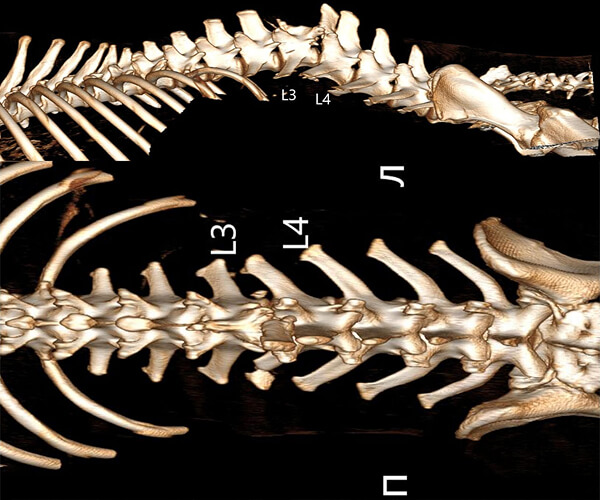

Именно в этот момент над Зухраем надругались люди. Сначала с него сдирали кожу по бокам. Потом били по спине. А позже — выстрелили. На КТ видно: в теле Зухрая застряли пули, позвоночник повреждён, задние лапы отказали. Судя по снимкам, спинной мозг разорван. Сегодня он не может лечь. Он спит и ест только сидя, каждую минуту испытывая боль.